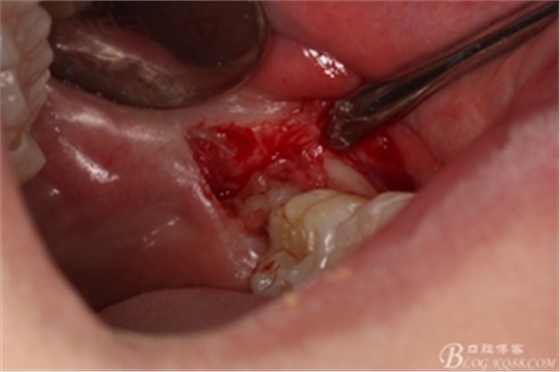

圖6.麻醉效果確定后,在37的近中做垂直松弛切口+遠(yuǎn)中水平切口

圖7. 遠(yuǎn)中的水平切口

圖8. 翻瓣:建議翻小瓣

圖9.翻開(kāi)瓣,可見(jiàn)38部分牙冠暴露